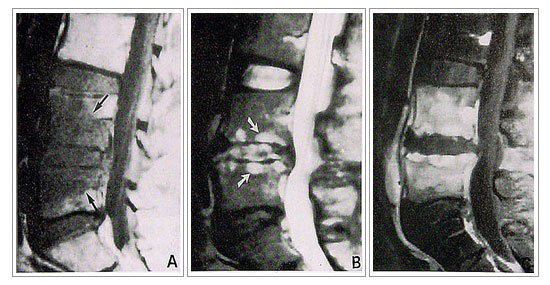

- 화농성 척추염

가장 흔한 균으로 황색포도상구균(박테리아)에 의해 염증이 생기는

질환이며 급성기에는 발열 등 화농성 질환에 따르는 증세와 함께 국소적인 등 허리의 통증이

심하며 내버려두면 패혈증으로 발전해 사망할 수도 있습니다. 초기에는 결핵성척추염과 구별이

어렵습니다. |

1)

진단

| |

- 단순방사선

- 골스캔 및 컴퓨터 단층촬영

- 자기공명영상 |

2)

치료

| |

- 비수술적 치료 ; 항생제 + 환부고정(보조기)

- 수술적 치료 ; 전방접근법을 통한 농양 및 변연 절제술, 척추골재건 및 변형교정을

위한

자가 골이식과 임플란트 내고정술 |